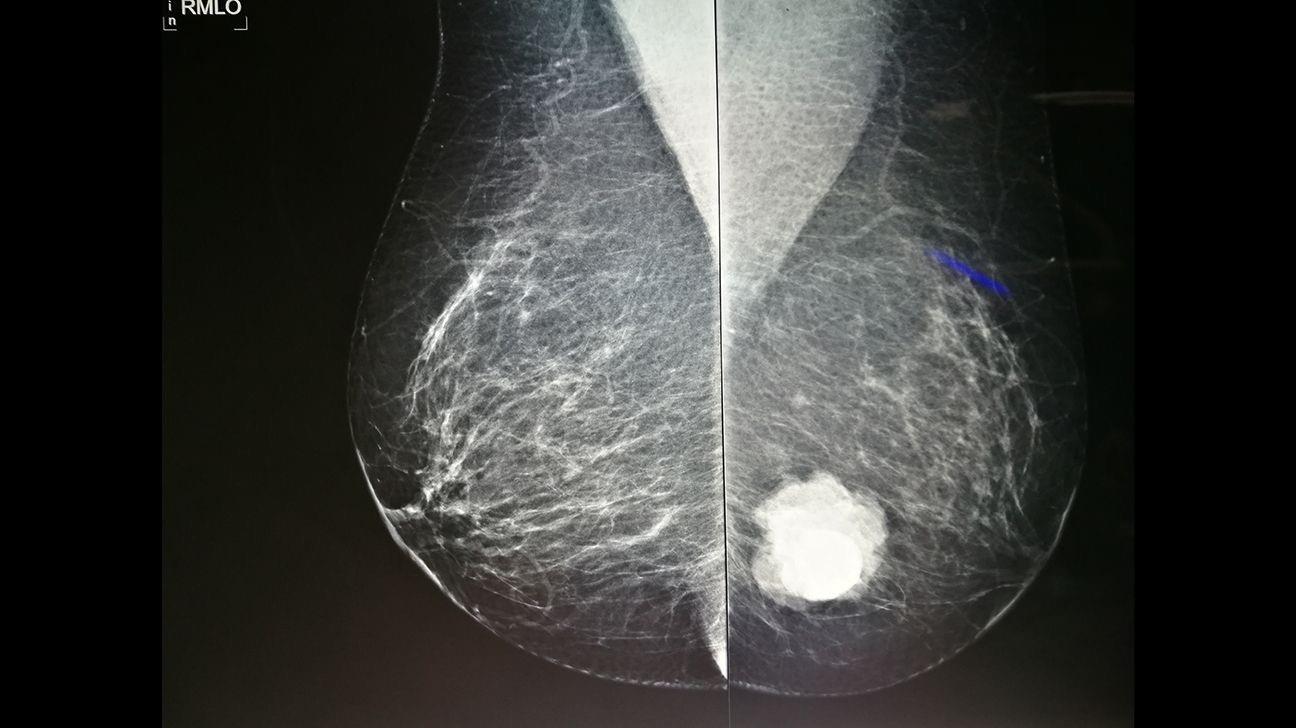

L'immunothérapie révolutionne la lutte contre les cancers agressifs

Actuellement, env 50 millions de personnes luttent contre le cancer, mais seulement la moitié survivront à la prochaine décennie Pour les cancers les plus agressifs, les traitements conventionnels tels que la radio/chimiothérapie et la chirurgie ne suffisent pas et sont souvent très toxiques Les immunothérapies sont des alternatives prometteuses qui exploitent notre propre système immunitaire pour tuer les cellules cancéreuses Les thérapies cellulaires immunitaires sont une sorte d’immunothérapie «vivante», où des globules blancs (cellules immunitaires) sont récoltés, renforcés (ou reprogrammés) en laboratoire, puis réinjectés pour traquer et détruire le cancer Pour les cancers récidivants les plus meurtriers, 60% des patients vivent désormais jusqu'à 5 ans, et 30% sont considérés comme guéris grâce à ces nouvelles technologies Mais 30%, ce n'est pas assez et cela reste encore très cher

Les immunothérapies actuelles sont coûteuses et souffrent d’une efficacité incomplète